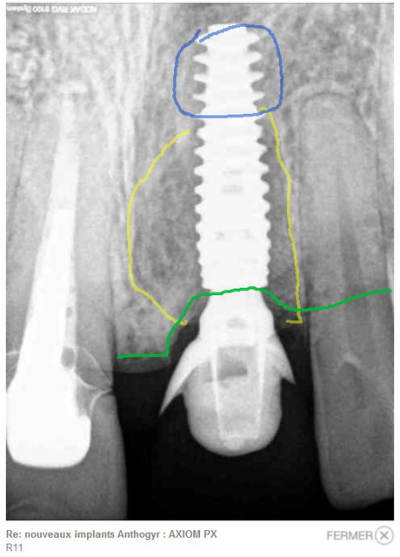

Sur la radio post-op, j'ai dessiné la région où tu aggripes en apical (bleu), la zonne comblée (jaune) et le niveau osseux (vert).

> Sur la radio post-op, j'ai dessiné la région où tu aggripes en apical (bleu), la

> zonne comblée (jaune) et le niveau osseux (vert).